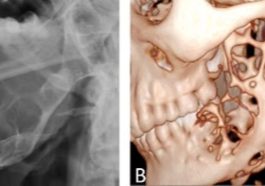

Ameloblastoma: Tumor Jinak Rahang yang Perlu Diwaspadai

Lee Gay Lord - Ameloblastoma adalah jenis tumor jinak yang berkembang pada rahang, terutama di area mandibula (rahang bawah). Meskipun…